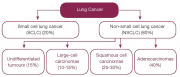

| 10:17, 4 באוגוסט 2014 | סוגי סרטן ריאה.png (קובץ) |  |

77 קילו־בייטים | Motyk | 1 | |